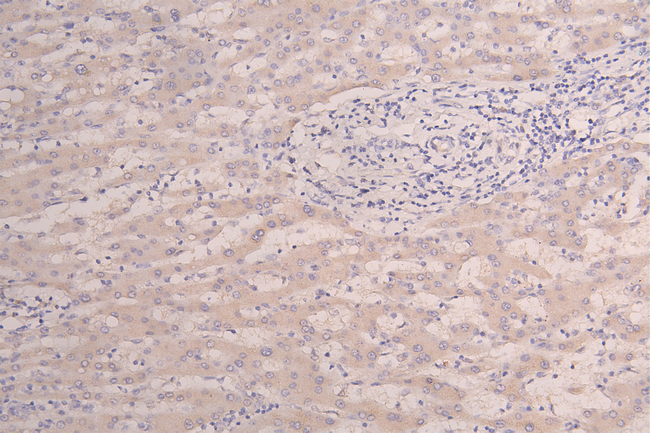

IHC image of CSB-RA010327MA1HU diluted at 1:100 and staining in paraffin-embedded human Liver tissue performed on a Leica BondTM system. After dewaxing and hydration, antigen retrieval was mediated by high pressure in a citrate buffer (pH 6.0). Section was blocked with 10% normal goat serum 30min at RT. Then primary antibody (1% BSA) was incubated at 4°C overnight. The primary is detected by a Goat anti-Human IgG labeled by HRP and visualized using 0.05% DAB.

IHC image of CSB-RA010327MA1HU diluted at 1:100 and staining in paraffin-embedded human Liver cancer performed on a Leica BondTM system. After dewaxing and hydration, antigen retrieval was mediated by high pressure in a citrate buffer (pH 6.0). Section was blocked with 10% normal goat serum 30min at RT. Then primary antibody (1% BSA) was incubated at 4°C overnight. The primary is detected by a Goat anti-Human IgG labeled by HRP and visualized using 0.05% DAB.

IHC image of CSB-RA010327MA1HU diluted at 1:100 and staining in paraffin-embedded human kidney tissue performed on a Leica BondTM system. After dewaxing and hydration, antigen retrieval was mediated by high pressure in a citrate buffer (pH 6.0). Section was blocked with 10% normal goat serum 30min at RT. Then primary antibody (1% BSA) was incubated at 4°C overnight. The primary is detected by a Goat anti-Human IgG labeled by HRP and visualized using 0.05% DAB.